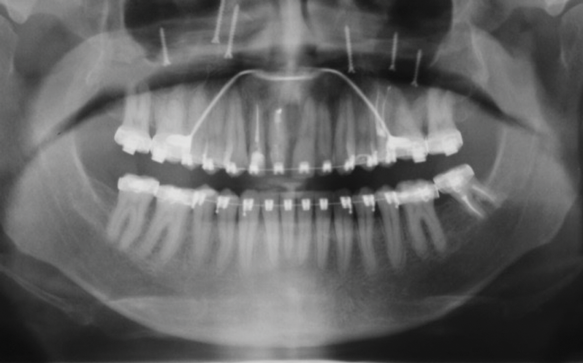

Fig 9. A class III adult male patient required surgical orthodontic treatment. The patient had anterior and posterior crossbites and required leveling of a deep curve of Spee during presurgical orthodontics.

Figure 9

Fig 10. A class III adult male patient required surgical orthodontic treatment. The patient had anterior and posterior crossbites and required leveling of a deep curve of Spee during presurgical orthodontics.

Figure 10